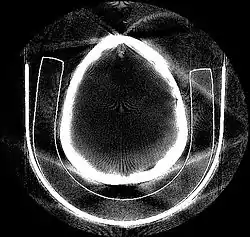

Le théorème de projection de Radon établit la possibilité de reconstituer une fonction réelle à deux variables (assimilable à une image) à l'aide de la totalité de ses projections selon des droites concourantes. L'application la plus courante de ce théorème est la reconstruction d'images médicales en tomodensitométrie, c'est-à-dire dans les scanneurs à rayon X. Il doit son nom au mathématicien Johann Radon.